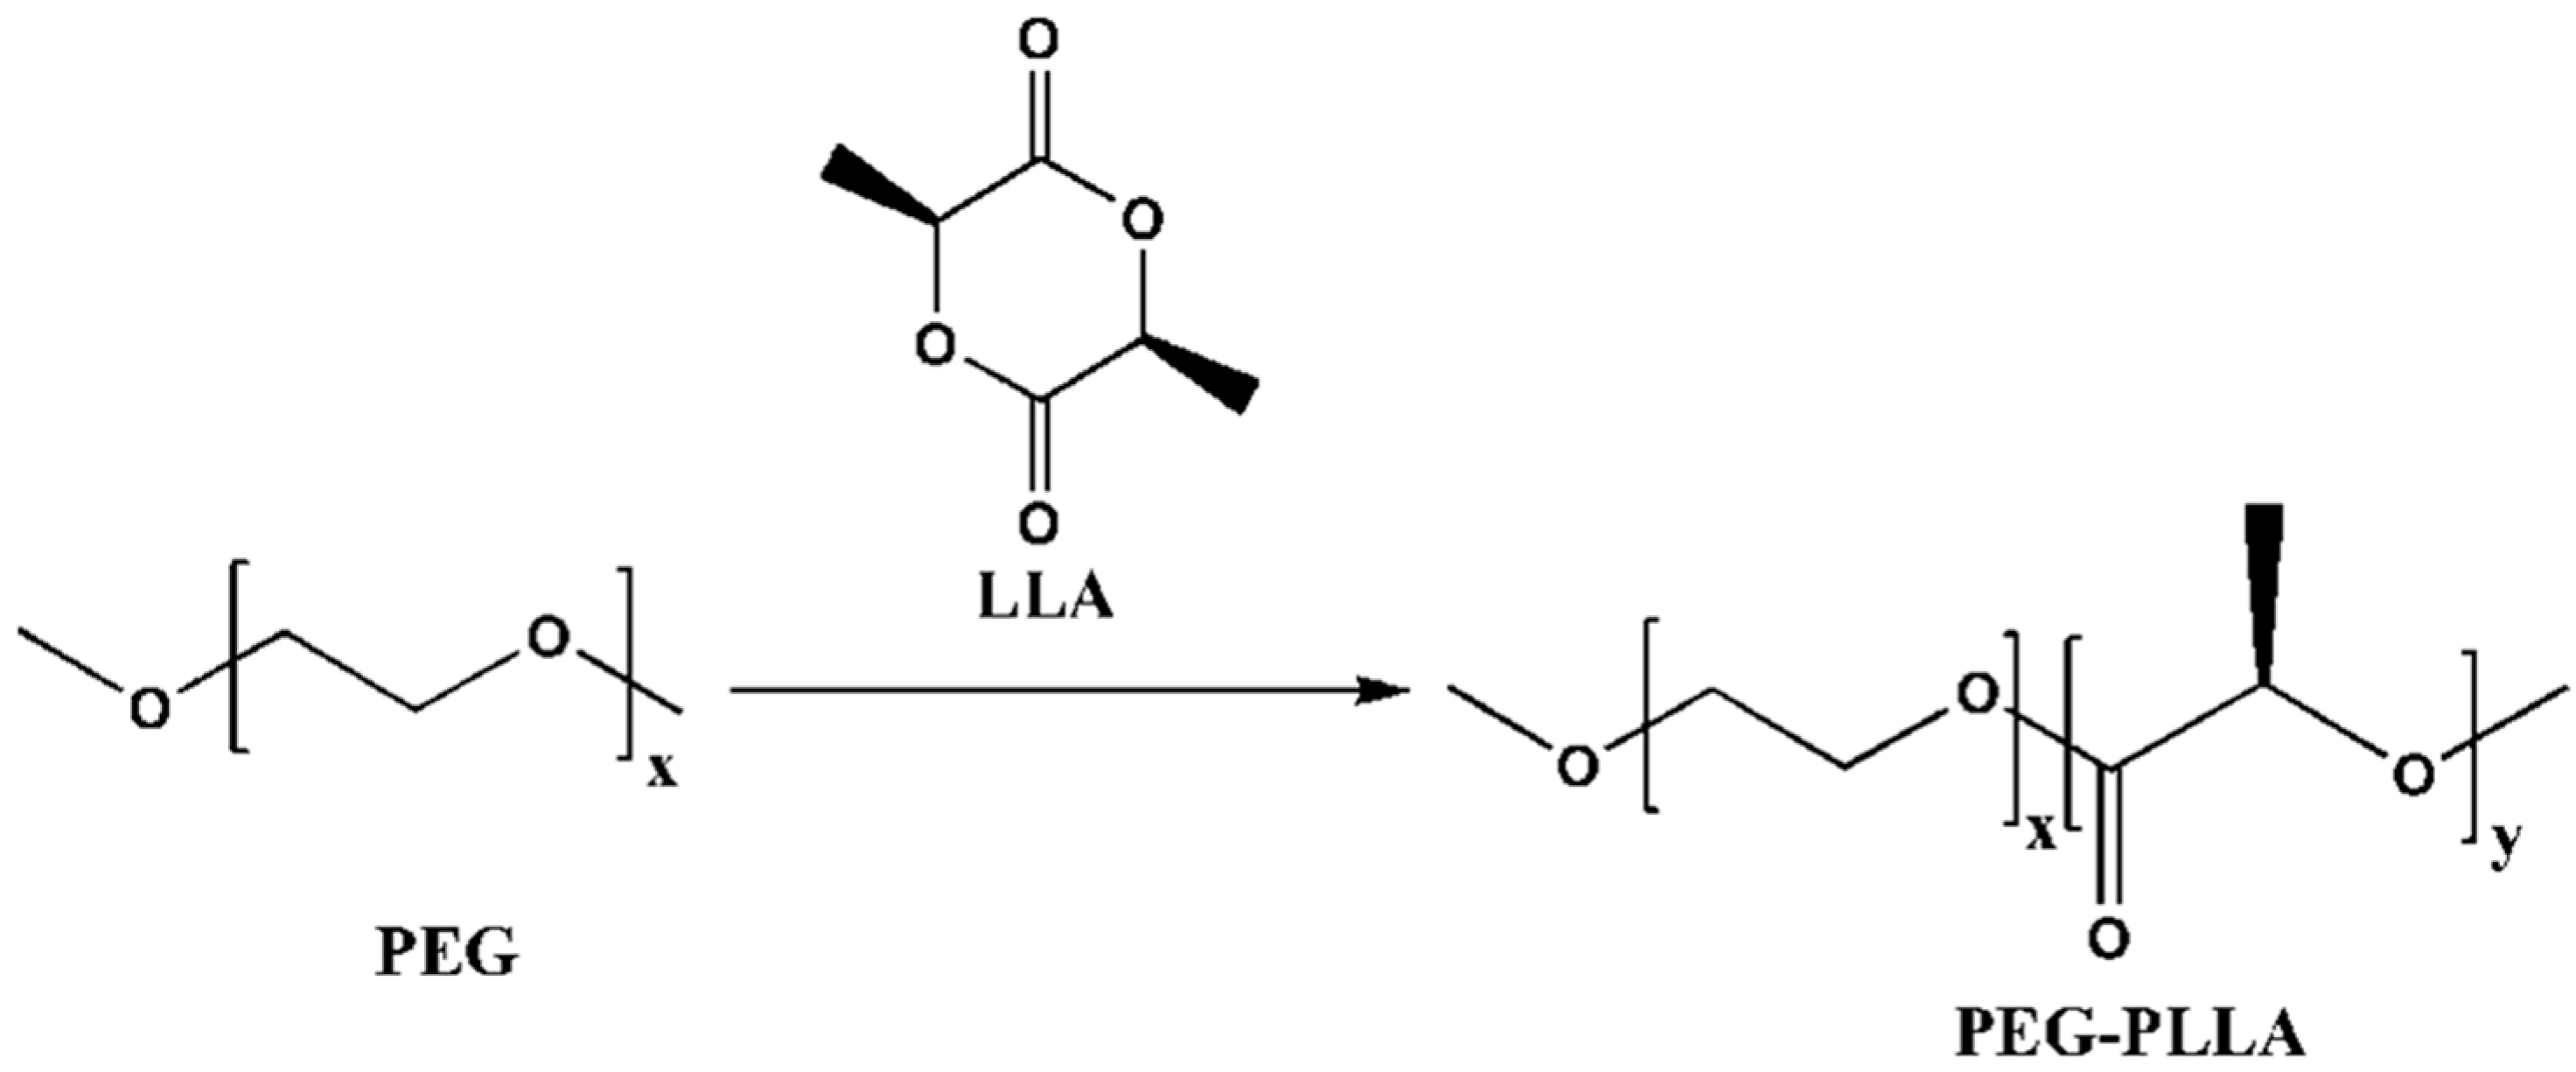

2.2. The Synthesis of PEG-PLLA Diblock Copolymer

3.1. Characteristics of PEG-PLLA Copolymer